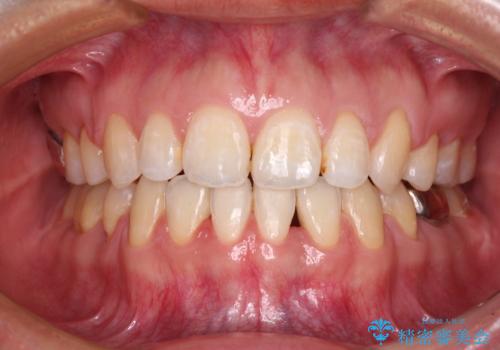

- 上下前歯を部分矯正したところ出っ歯になってしまったとのことで来院された患者様です。

上下左右第一小臼歯4本を抜歯して、積極的に口元を引っ込めるよう、ワイヤー装置にて矯正治療を行うこととしました。